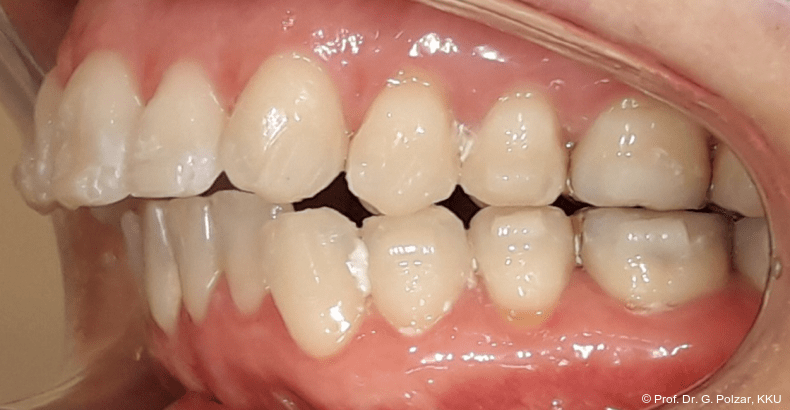

Diese deutlich anteriore Gelenkposition im Neutralbiss ließ den Verdacht auf einen Sunday Bite zu. Das heißt, die Patientin schob den Unterkiefer aktiv nach vorne, um damit schönere Schneidezahnkontakte bzw. eine vermeintlich neutrale Okklusion zu erreichen. Nach mühsamen Lockerungsübungen gelang es der Patientin, auch in die zen­trale Kiefergelenkposition zu wechseln. So zeigte sich das ganze Ausmaß der Malokklusion. In neutraler KG-Position hatte die Patientin eine sagittale Frontzahnstufe von ca. 7 mm mit 1 PB Klasse II-Okklusion im Seitenzahn­bereich (Abb.5a+b, 7a–c).